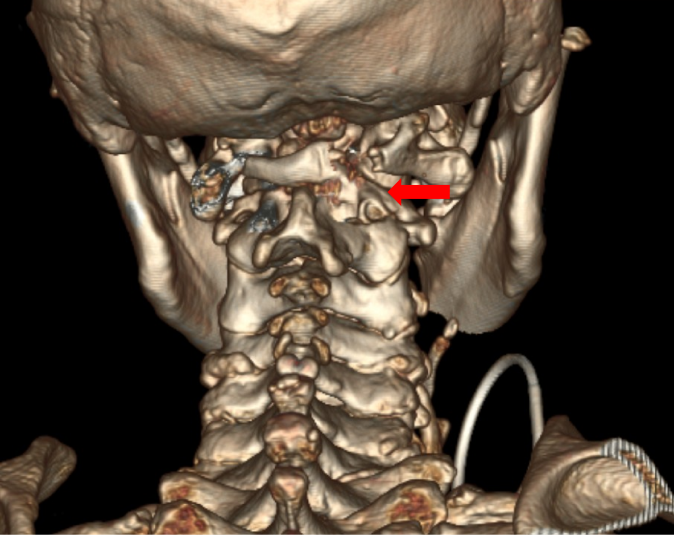

图3:术后复查CT见骨性减压充分

患者苏醒后四肢便能恢复活动,经过3天短暂的应急反应期,四肢功能对比术前得到改观。在张霞芬护士长领衔的护理团队精心护理下,患者两周后顺利出院。术后1个月门诊复查显示尽管步态还有异常,但患者已能独立行走,原先无法举起的左上肢也可以举过肩了。患者术后3月,行走已经接近正常,患者及家属对治疗效果非常满意。